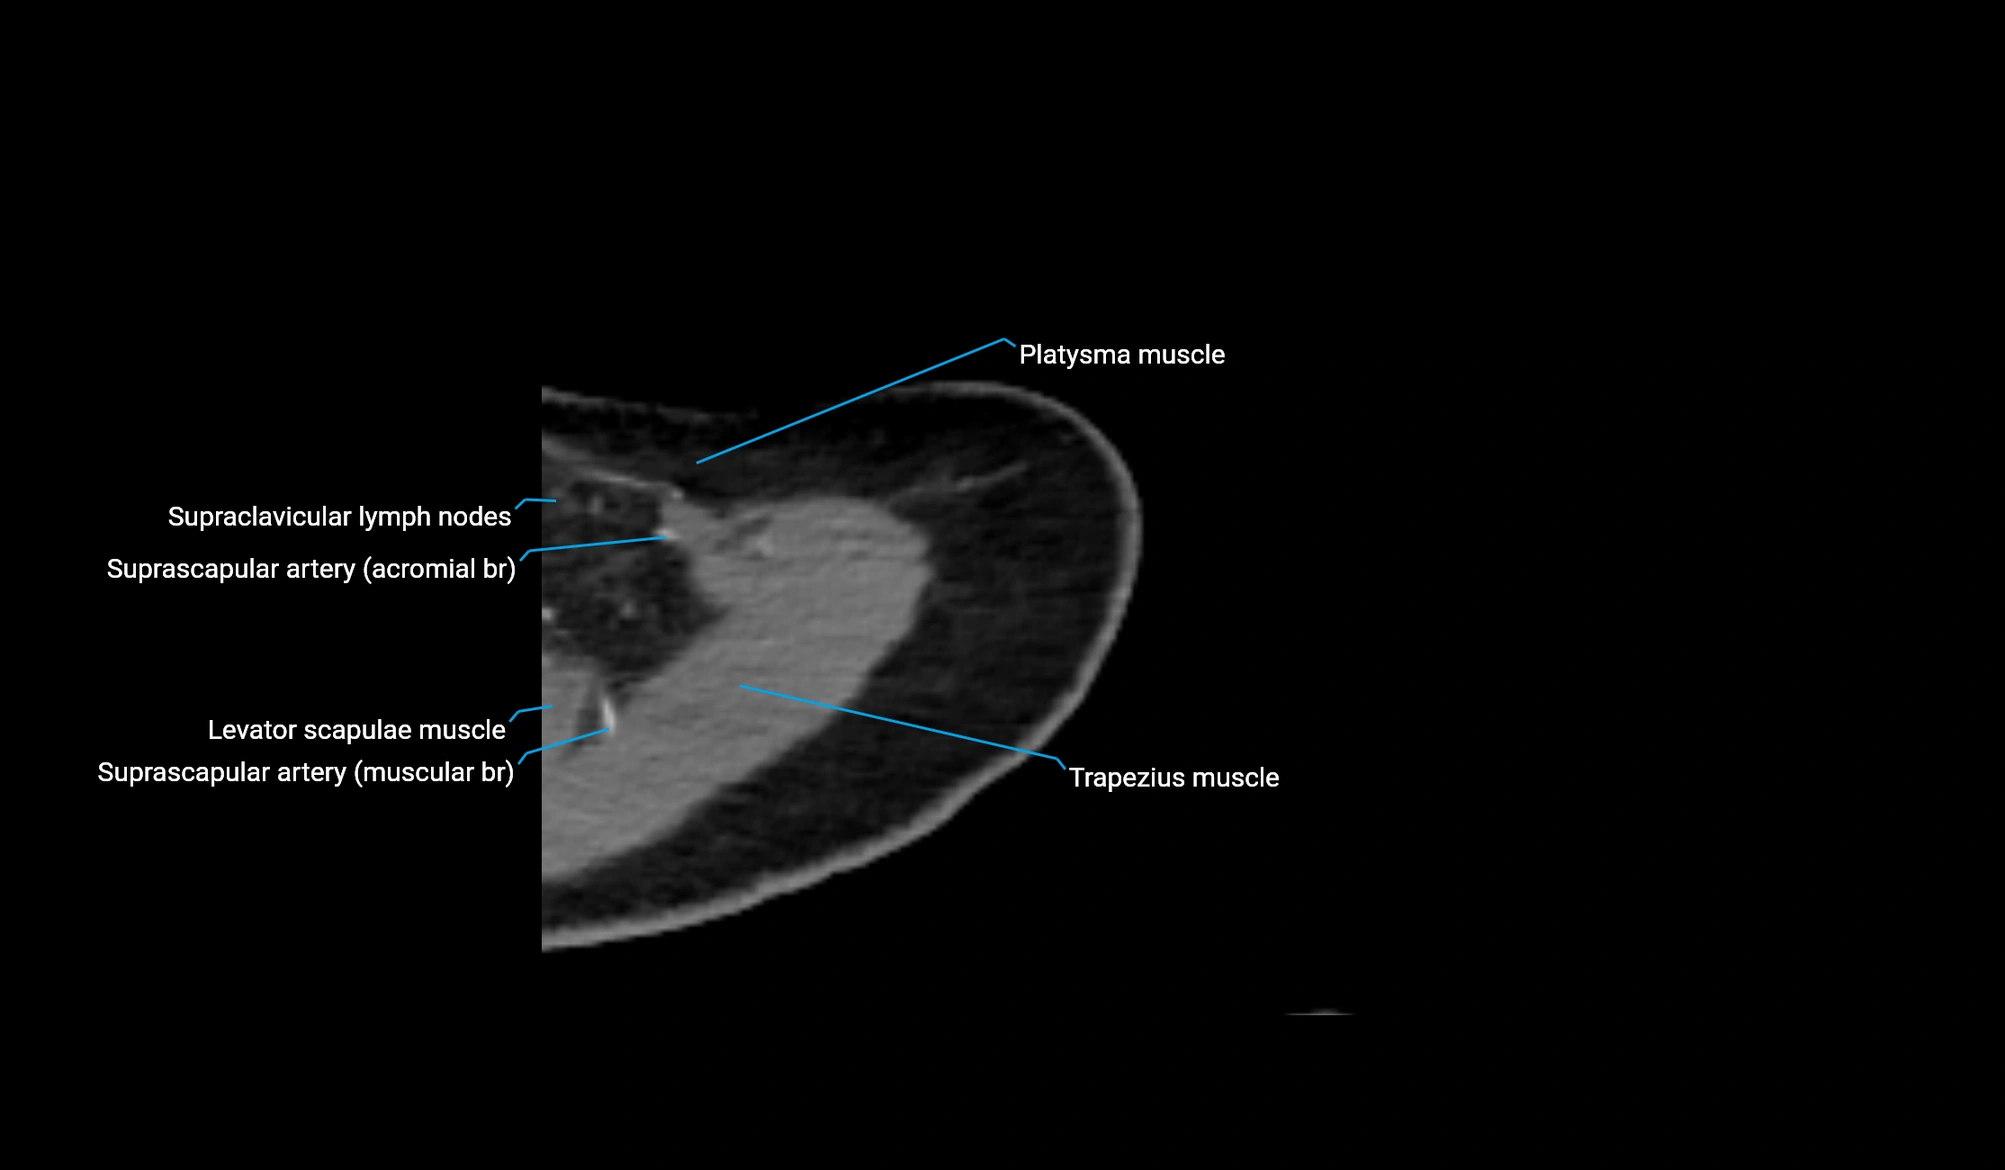

- Inferior belly of omohyoid muscle

- Spine of scapula

- Subscapularis muscle

- Superior angle of scapula

- Supraspinatus muscle

- Trapezoid ligament